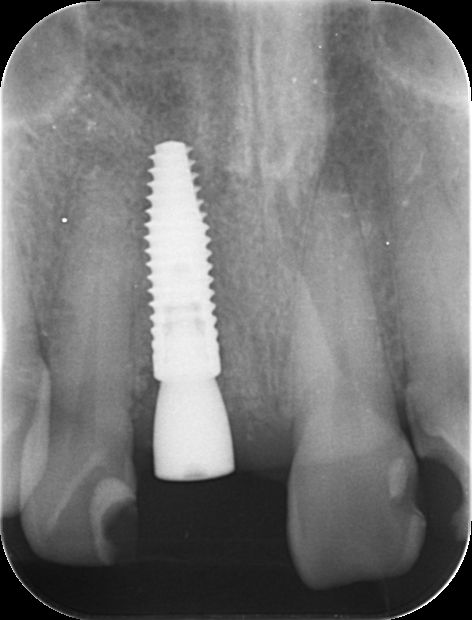

レントゲンを見てみると歯根(歯の根の部分)が黒く溶けていることが分かり、抜歯と診断しました。

前歯のインプラントはとても難しく技術がないと歯茎が下がってしまったりと不具合が出てしまいます。

X-ray

処置後、非常に審美的な補綴物が入ったことが分かるかと思います。